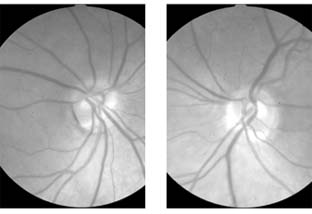

Figure 14-24

Figure 14-24: Bilateral tilted optic disks.

Tilted disks, which occur in 3% of normals, may also be seen with hypertelorism or the craniofacial dysostoses (Crouzon's disease, Apert's disease). They are oval disks with usually an inferior scleral crescent and an associated area of fundus hypopigmentation (Figure 14-24). They may be mistaken for papilledema. They may also produce predominantly upper temporal field defects, which may be mistaken for bitemporal loss due to chiasmal dysfunction. Scleral crescents are particularly common in myopic eyes.